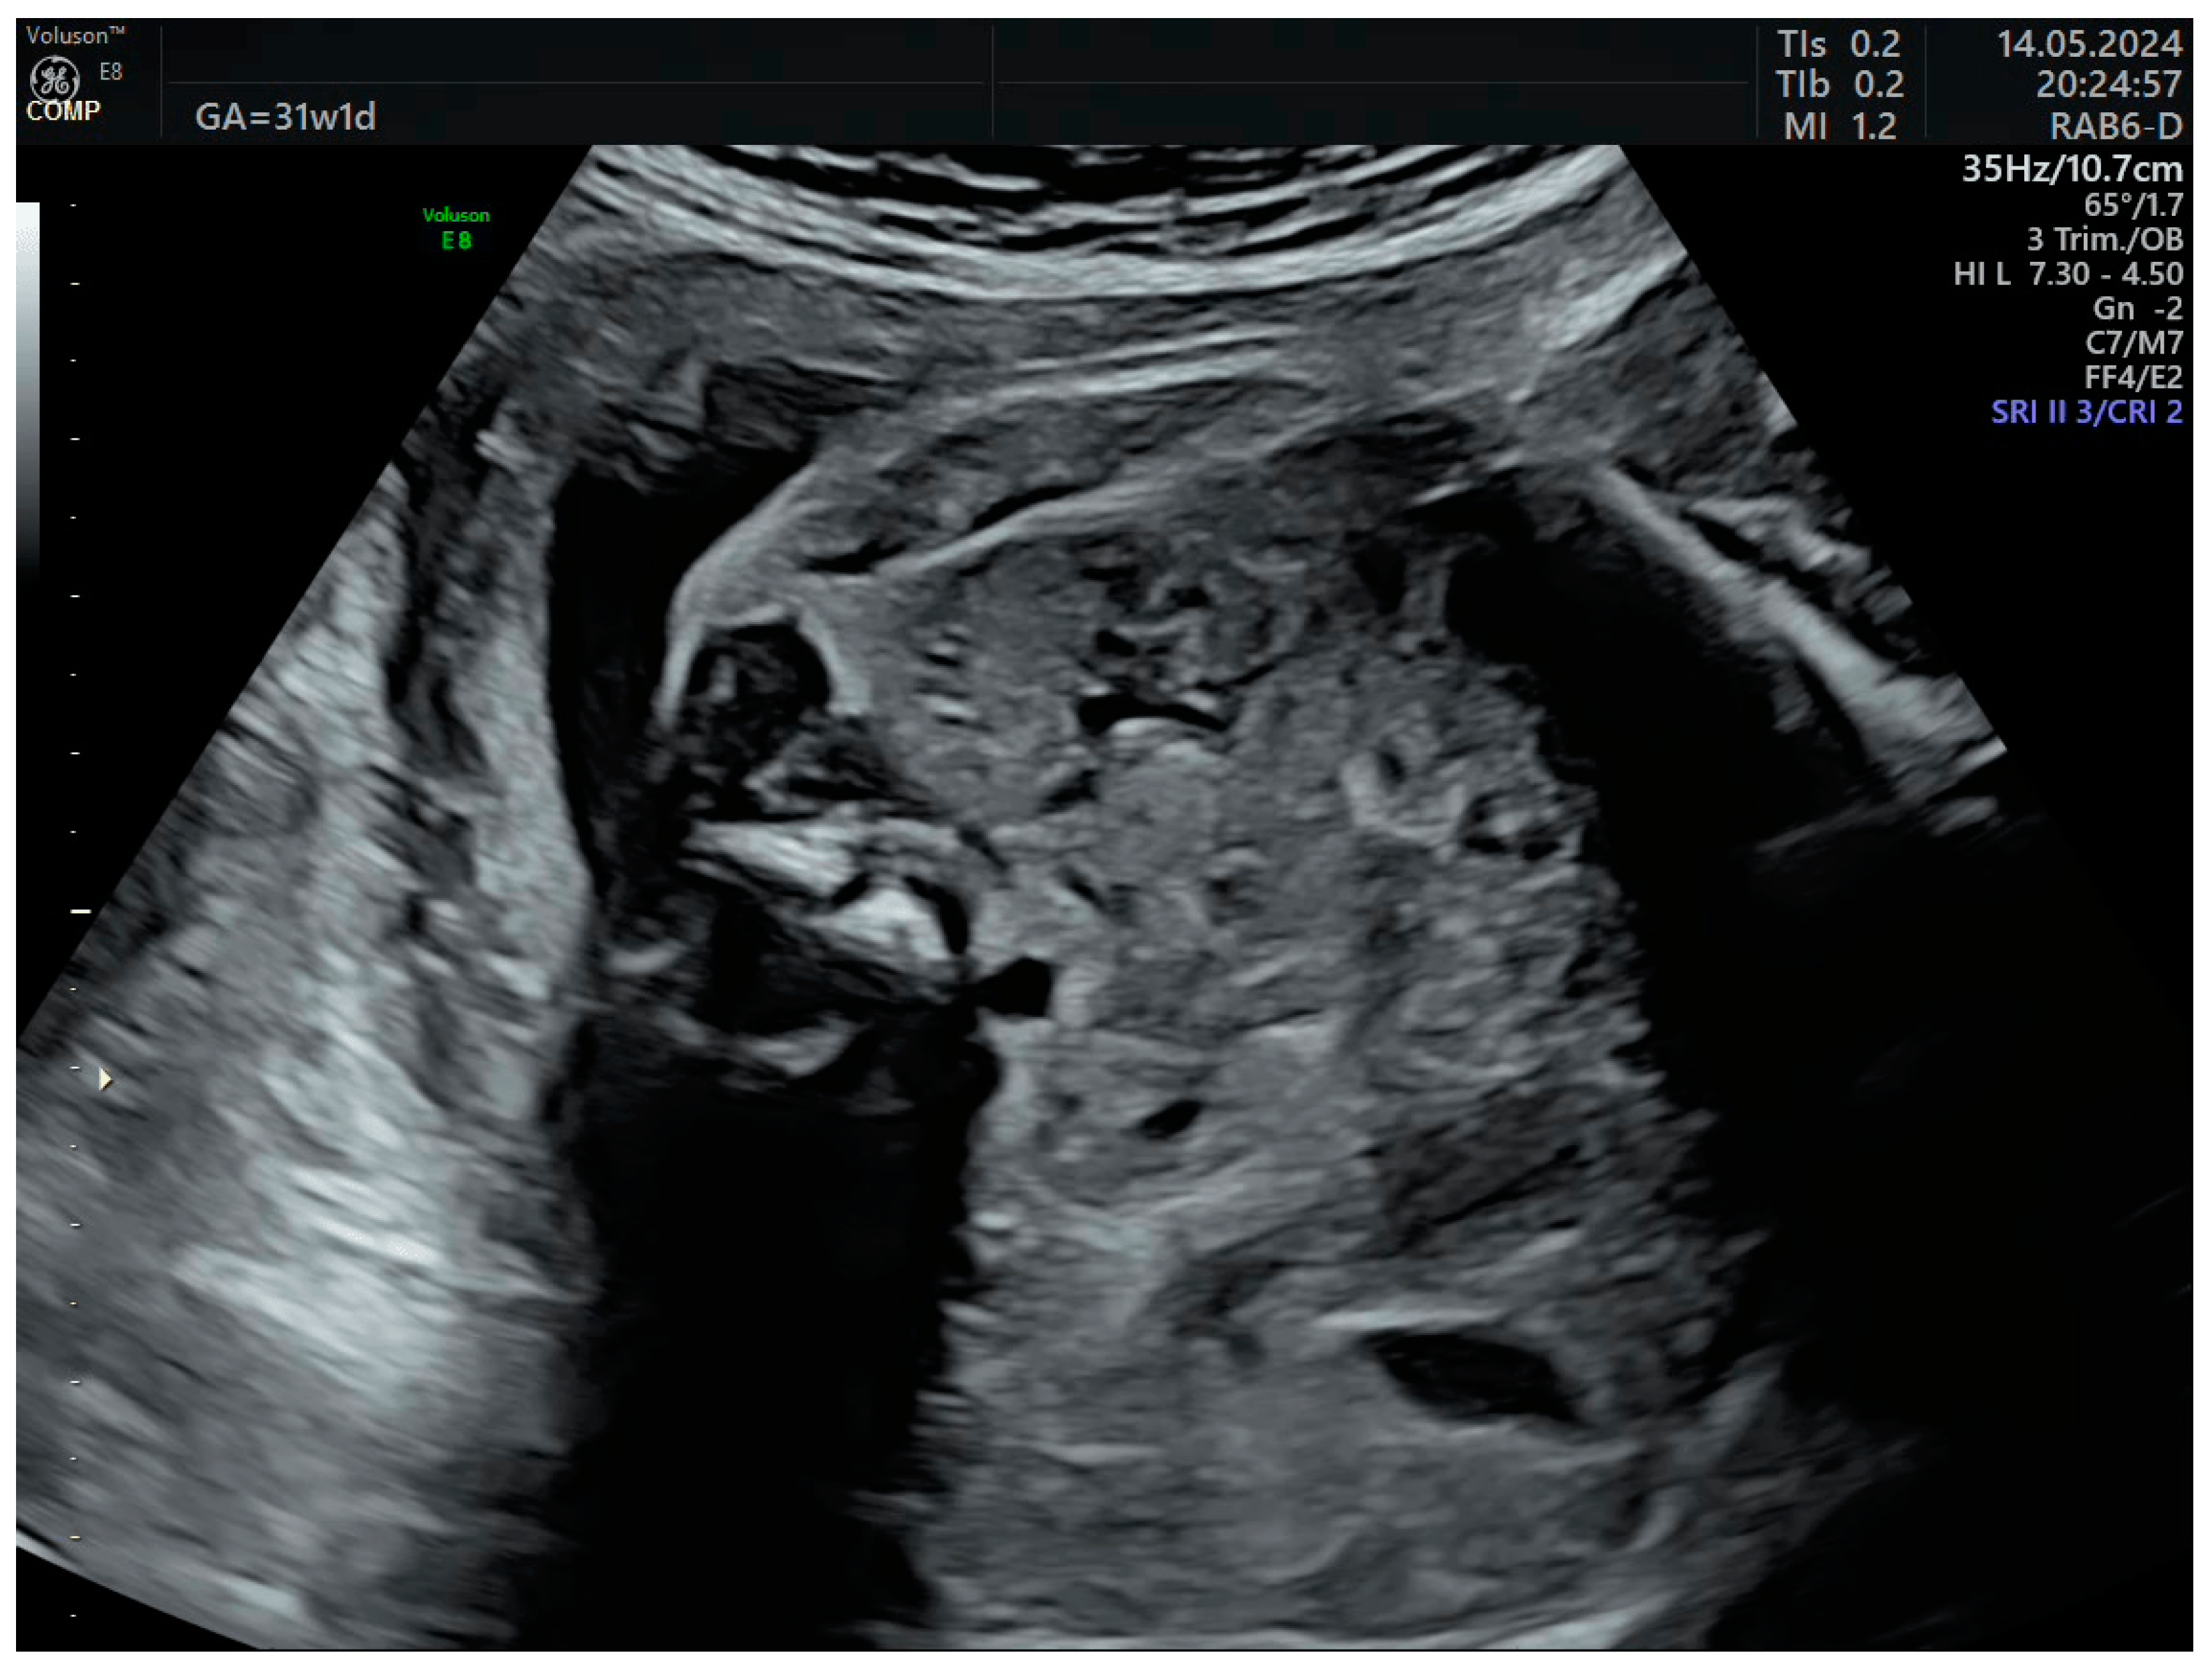

The third-trimester ultrasound evaluation at 31 weeks and 5 days confirmed once again the presence of crossed fused renal ectopia. Although the frequency of the associated changes (hydronephrosis, calyceal dilatations, ureteral dilatations, ureterocele, oligohydramnios, vesicoureteral reflux, etc.) in the third trimester is relatively high, none of these complications were present at the time of examination (Figure 7 and Figure 8). No other anomalies or deviations from the fetal growth curve were recorded, even though, starting from the 28th week, the patient developed diet-controlled gestational diabetes. The final diagnosis was isolated crossed fused renal ectopia.

Figure 8. Crossed fused renal ectopia in the third trimester without calyceal or pelvic dilations.